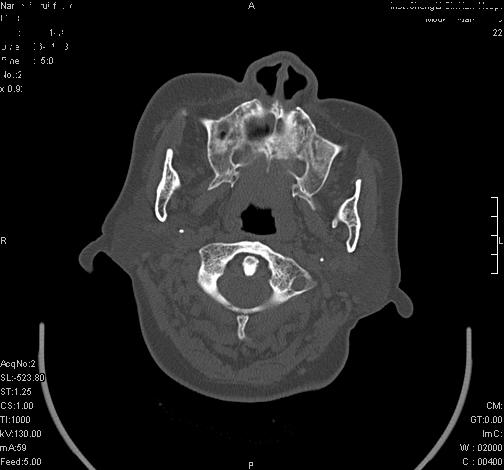

上次发的片子,不够细微。误导了大家,请大家再重新看一下,思路会更清晰。

双上颌窦高密度,其内见水样密度.考虑双上颌窦骨瘤伴上颌窦炎.

双上颌窦高密度,左侧病灶下部与左上颌窦底部骨质相延续,支持双上颌窦骨瘤

双侧上颌窦上部黏膜明显增厚、窦腔缩小,偏后侧窦壁骨质毛糙、模糊,窦腔内见条块状钙化。结合双侧鼻甲黏膜明显增厚,以及临床症状,

考虑:双侧上颌窦霉菌性鼻窦炎

双侧上颌窦密度增高,粘膜增厚,内见条片状钙化,窦壁无增生与破坏征象,双侧鼻甲粘膜肥厚.

意见:双侧霉菌性上颌窦炎.

温习:真菌性鼻旁窦ct特征 1)非侵袭性病变者可涉及到鼻腔和鼻窦,多为单侧,上颌窦最多见.2)ct示窦腔内软组织增生影,可呈息肉状,+c可强化3)增生软组织影内可见散在斑片状或沙砾状钙化区,此为其典型特点,4)

非侵袭性病变可见窦壁骨质增生,破坏少见;侵袭性病变可见窦壁骨质破坏.